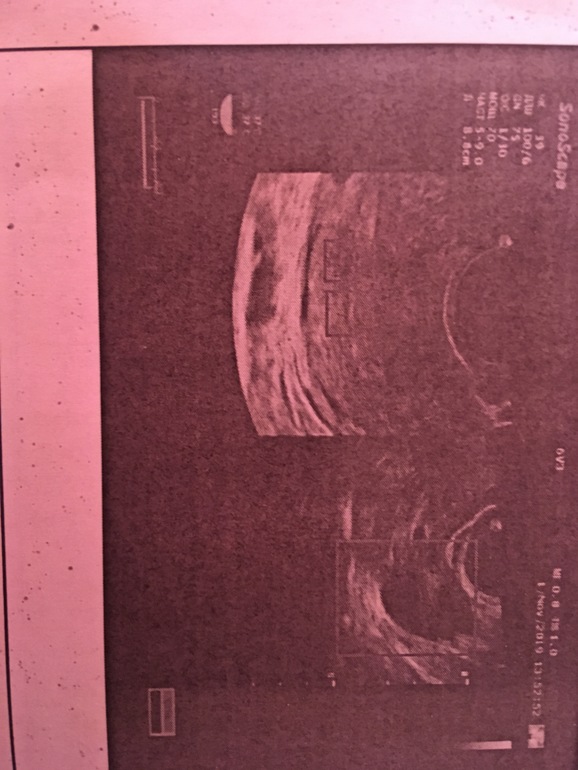

А что такого вам написали, чтобы грустить? Киста желтого тела? Так куча народу вынашивают с этим, и ничего. На 5дз уже ПЯ! У вас ранняя овуляция была? Если видно ПЯ, то хгч уже высокий. Ну и да - для эмбрионов еще слишком рано. У вас двойня, а вы грустите, зачем? Не надо отрицательную энергию им передавать.

У меня была ранняя овуляция. За два дня до м была на УЗИ. Увидели точку. Но не страшила и не писала что не визуализируется. Говорит что рано пришла. Но хгч точно сдавайте